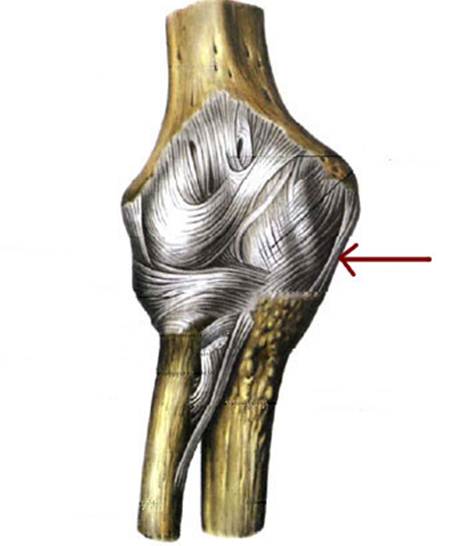

S: Стрелка указывает на lig. Collateralis ulnare

S: Стрелка указывает на lig. Anulare radii

S: Стрелка указывает на lig. Collaterale radiale